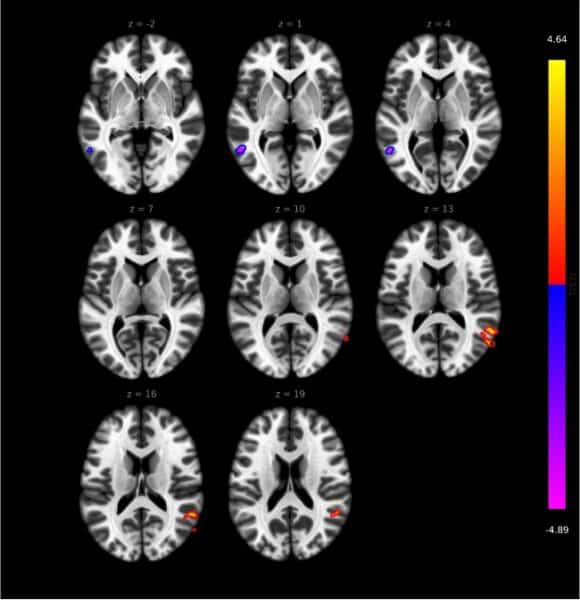

The study involved 30 difficult-to-treat and 20 non-difficult-to-treat RA patients, as well as 30 healthy controls. The tests included a comprehensive clinical assessment, psychological analysis, functional MRI, and transcriptomic (high-throughput analysis of RNA molecules transcribed from the genome in different organs, tissues, cell types, and under different conditions) and metabolomic analyses (analysis of “chemical fingerprints” left behind by specific cellular processes). The research has shown that in patients with difficult-to-treat RA, inflammatory activity, chronic pain, and the associated psychological burden also affect the central nervous system, Dr. Lilla Gunkl-Tóth explained in summary. Exploring the relationship between inflammation, pain, and psychological factors and identifying signal transmission pathways may help in the future development of treatments, the researcher emphasized.

Dr. György Nagy added that this finding could bring about a fundamental change in perspective, as RA has been treated primarily as a joint disease until now. He said that the current results represent a major step forward: The research sought to highlight that the disease also leaves a fingerprint in the brain, which could lead to significant changes in therapy. The director pointed out that the Department of Rheumatology and Immunology already treats RA patients in a unique way: In addition to drug therapy and steroids, non-drug treatment options also play a significant role.